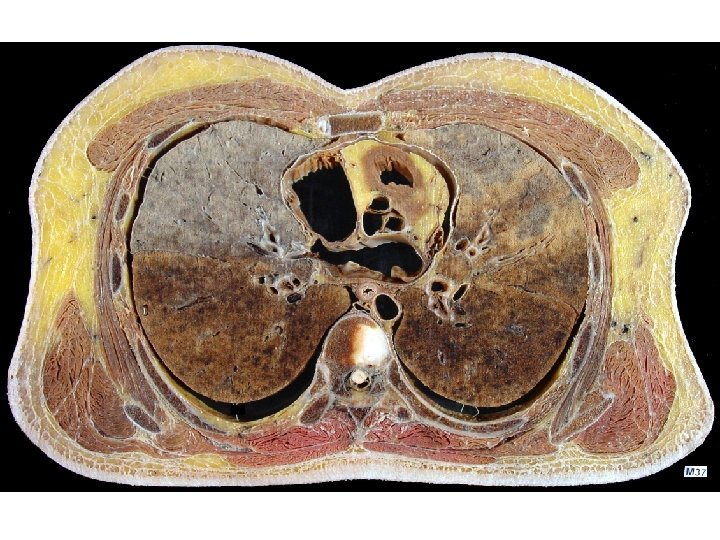

The Esophagus 食管 General features -a muscular tuber about 25 cm long, connecting the pharynx at level of C 6 vertebra, passes through the diaphragm at level of T 10 vertebra and after 1~2 cm enters the stomach Division: • Cervical part • Thoracic part • Abdominal part

Three constrictions • At its beginning, 15 cm from incisors, lies at level of C 6, is the narrowest part of the esophagus • Where it is crossed by left main bronchus, 25 cm from incisors, lies at level of intervertebral disc between T 4 and T 5. • Where it passes through the esophageal hiatus of diaphragm, 40 cm from incisors, at level of T 10